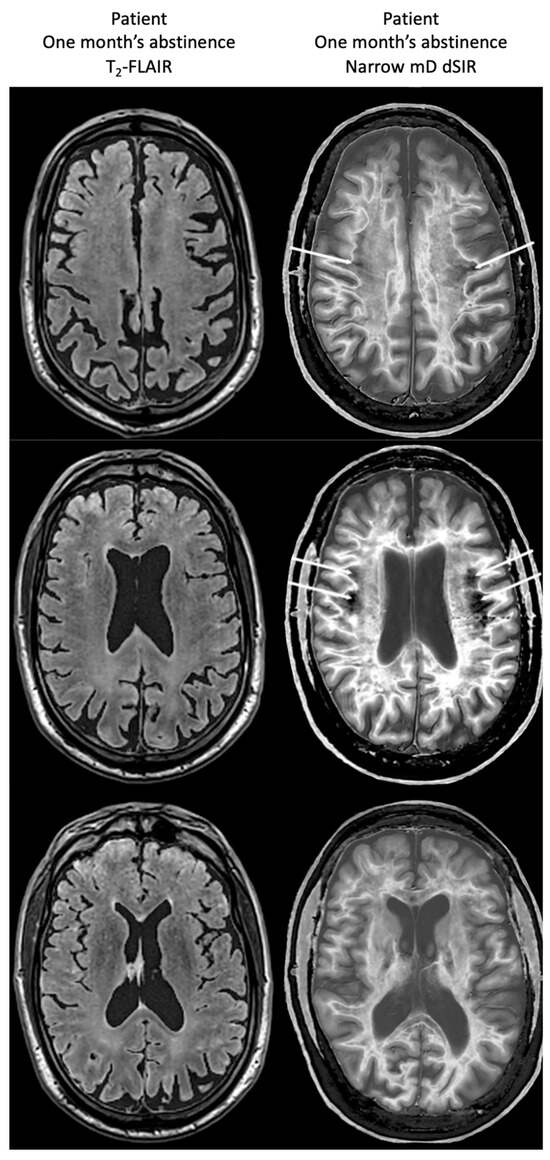

Figure 18 compares T2-FLAIR images (left column) with matched narrow mD dSIR images (right column) in Case 1 at the time of his first examination. No abnormality is seen in the white matter on the T2-FLAIR images (left column) but extensive high signal abnormalities are seen in white matter on the narrow mD dSIR images. Small areas of more normal white matter with a low signal appearance are shown by the white arrows (right column). These are features of a whiteout sign grade 4.

Figure 18.

Case 1 patient with methamphetamine use disorder. Comparison of T2-FLAIR and narrow mD dSIR images. No abnormality is seen on the T2-FLAIR images (left column) but there are extensive areas of higher signal in approximately 90% of the white matter (right column). Only small areas of normal low signal are seen in the white matter (white arrows) (right column). The appearances on the dSIR images are consistent with a whiteout sign grade 4.